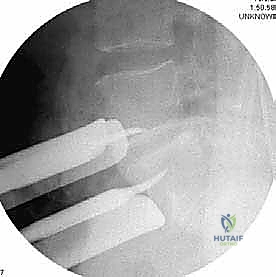

الخطوة 5: التثبيت (Fixation)

لضمان أقصى درجات الثبات والسماح للعظم بالاندماج بمرور الوقت، يتم تثبيت القفص باستخدام شريحة معدنية صغيرة ومسامير من التيتانيوم تُثبت في الأجسام الفقرية من الأمام. في بعض الحالات، قد يرى الدكتور هطيف ضرورة إضافة تثبيت خلفي بمسامير عبر الجلد (Percutaneous Pedicle Screws) لزيادة الدعم.

الخطوة 4: التثبيت القوي (Rigid Fixation)

نظراً لضخامة الفراغ الذي تم تعويضه، يتطلب الأمر تثبيتاً قوياً جداً. يتم استخدام شرائح تيتانيوم طويلة ومسامير من الأمام، وفي الغالبية العظمى من الحالات، يتطلب الأمر إجراء مرحلة ثانية لتثبيت العمود الفقري من الخلف بمسامير وقضبان لضمان استقرار البناء الجراحي بزاوية 360 درجة.